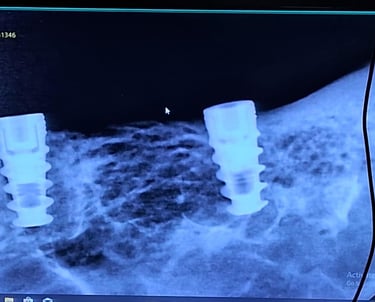

Implant dentistry uses titanium or ceramic posts placed in the jawbone to replace missing teeth. These implants act as artificial roots, supporting natural-looking, fixed or removable teeth.

Implant Dentistry